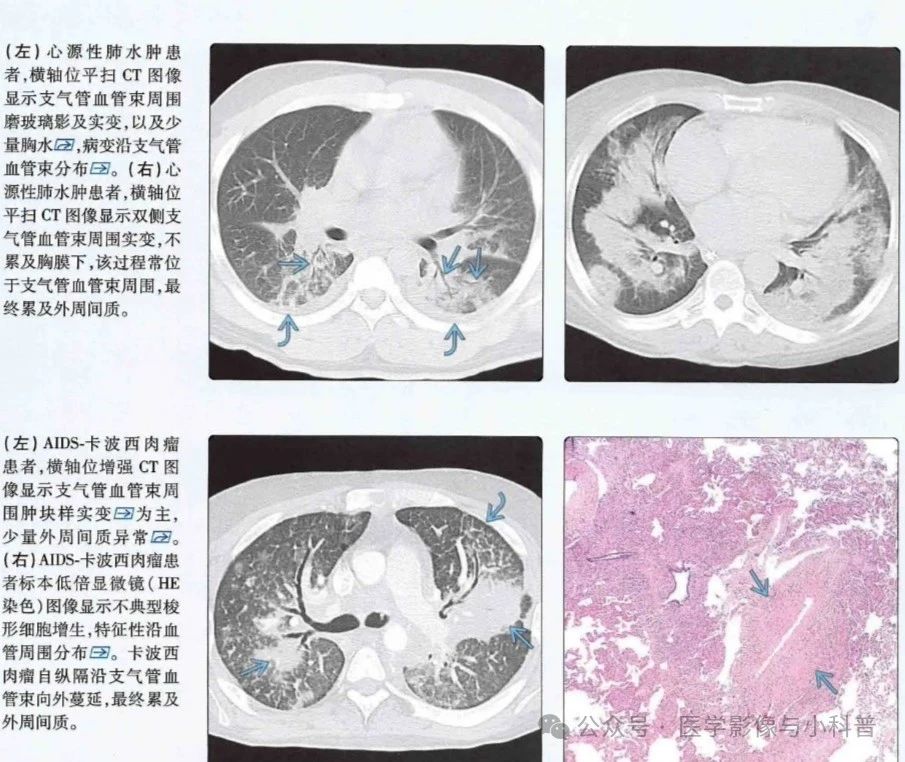

1.支气管血管束周围分布型   支气管血管束周围间质被水肿、血液、肿瘤、肉芽组织或气体浸润。表现为

①流体静力性肺水肿表现为支气管血管束周围增厚、磨玻璃、实变和间隔增厚

③卡波西肉瘤支气管血管束周围增厚、火焰状结节(即边缘模糊、不规则)

47bc92f209617eca7a1e4be792c8f14a.jpg

69fea9eb9c232de3529154e96657a75a.jpg